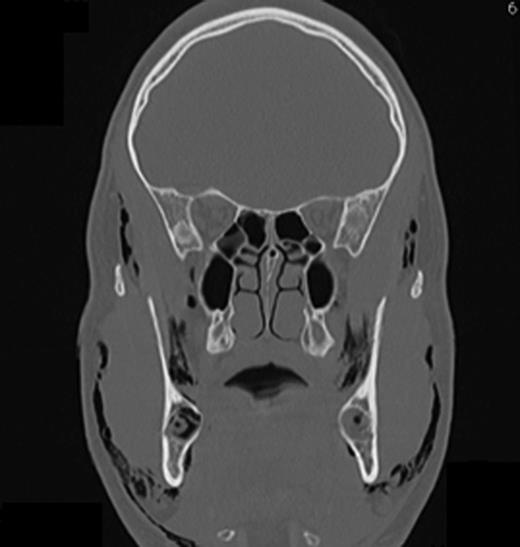

Computed tomography (CT) of the head and neck region revealed a bilaterally located subcutaneous air collection in the area of the periorbital, temporal, paramandibular and supraclavicular region (Figs 3–5). There were no signs or symptoms of severe complications such as pneumothorax or pneumomediastinum.

CT scan (coronal section in the first premolar region) showing multiple air inclusions within the facial soft tissue.